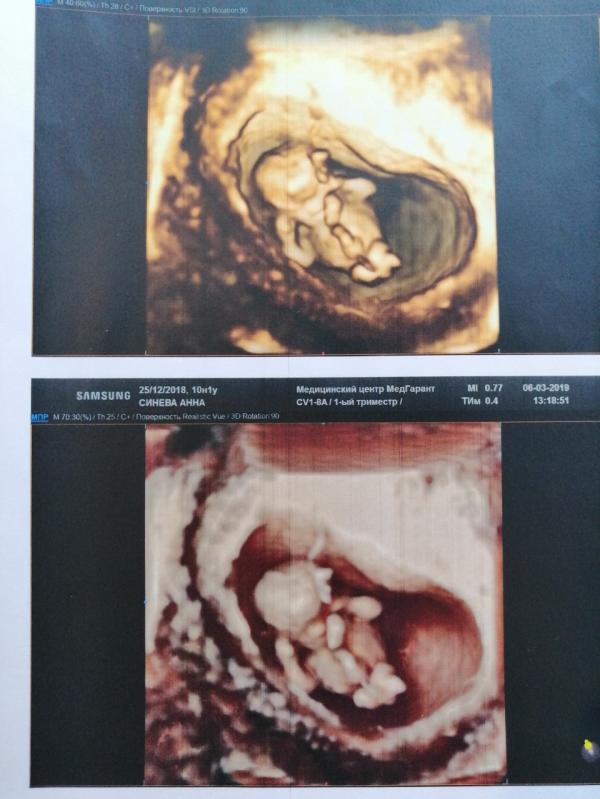

По месячным 10 недель 1 день. По УЗИ 10 недель 4 дня, опережает чуточку 💓

Обычное УЗИ, просто узист прекрасный 😍 несколько раз 3д включал))